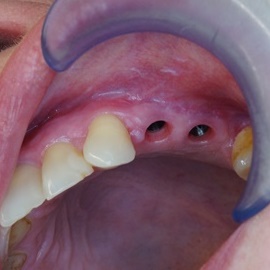

Pacjentka głosiła sie do naszego gabinetu do leczenia z osadzonym mikroimplantem w pozycji lewej dolnej dwójki. Siostrzany implant w pozycji prawej dolnej dwójki wypadł wcześniej, około 1,5 roku od implantacji. Odtworzono przedsionek i dziąsło rogowaciejące, osadzono dwa implanty, jednoczasowo z regeneracją kości. Dopiero na etapie ostatecznej rekonstrukcji protetycznej usunięto zachowany mikroimplant. To się nazywa motywacja do leczenia! Pacjentka przygotowywała sie na ślub prawnuczki :)

implanty stomatologiczne implanty stomatologiczne implanty stomatologiczne implanty stomatologiczne